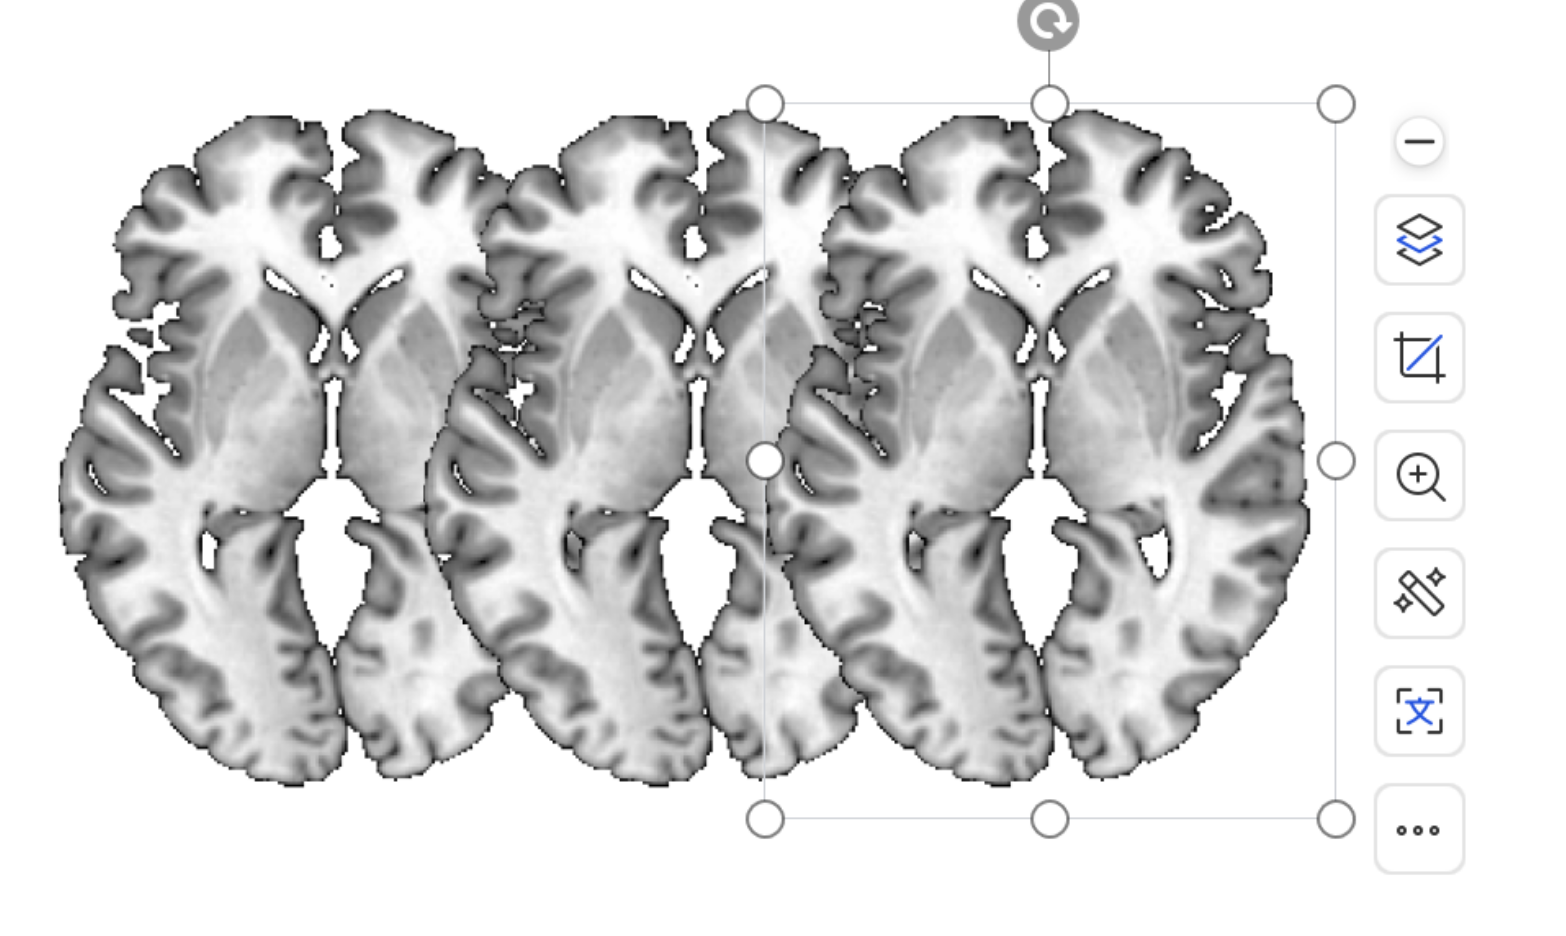

在菜单栏中点击Window -- Multislice

在View -- Slices 中可以改变所要展示的层数

在View -- Ocerslice中可以改变层数之间的重叠程度

点击Display -- Mosaic

左侧可以设置加载的层数